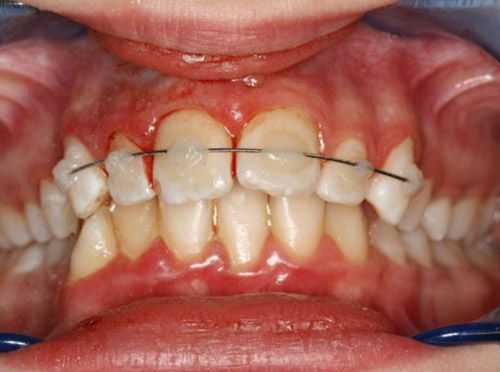

(Слева) На панорамной рентгенограмме у пациента с двухлоронним передним вывихом визуализируется правый мыщелок, смещенный кпереди и кверху относительно сулавного возвышения. Обратите внимание на явный передний открытый прикус, в то время как моляры находятся в окклюзии.

(Справа) На панорамной рентгенограмме у этого же пациента определяются аналогичные изменения слева. Открытый прикус обусловлен неправильным передним положением мыщелка, контакт задних зубов - его верхним положением.

(Слева) На рентгенограмме в боковой проекции у этого же пациента определяется прогнатическое положение нижней челюсти и открытый передний прикус вследлвие передне-верхнего смещения мыщелков нижней челюсти.

о Открытый прикус, отклонение нижней челюсти, преаурику-лярный отек

о Отсутствие твердых структур/углубление спереди от козелка